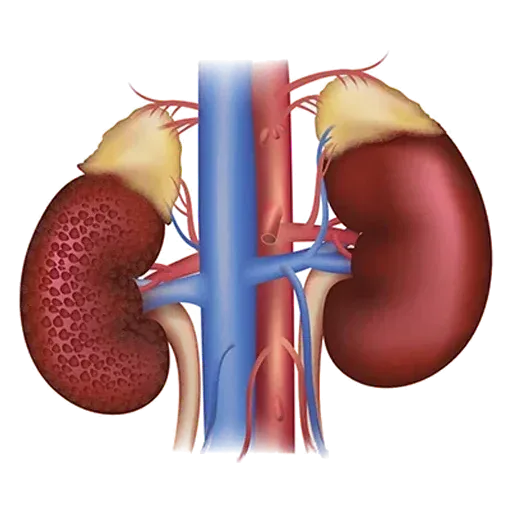

Restore Kidney Naturally

Complete Treatment for Stage 1-5 & Kidney Dialysis

Our Complete Treatment for Kidney Dialysis Kit is a holistic Ayurvedic solution designed to support kidney health and enhance overall well-being. Available in three convenient packages—365 days, 243 days, and 182 days—this treatment provides a blend of potent Ayurvedic medicines and herbal formulations known for their diuretic, antioxidant, and anti-inflammatory properties. The kit works synergistically to promote detoxification, enhance blood filtration, maintain fluid and electrolyte balance, and reduce inflammation, supporting the kidneys’ natural functions. Carefully crafted to address the challenges of dialysis, this kit offers a safe, effective, and sustainable approach to improving kidney health and reducing dependency on external interventions.

Ayurveda utilizes specific herbs and herbal formulations that are believed to benefit kidney health. These herbs, such as Punarnava, Gokshura, and Varunadi Kwath, are often used for their diuretic, anti-inflammatory, and antioxidant properties. They may help flush toxins, reduce inflammation, and support the kidneys’ overall function.

We, “Medilux Lifecare”, are a highly reputable Ayurvedic brand providing ayurvedic treatment for kidney infections alongside various lifestyle disorders worldwide. We utilize 100% ayurvedic herbs for kidney issues, respiratory concerns, gastrointestinal problems, and numerous other ailments at Medilux Lifecare Hospital, complemented by a well-balanced diet for our patients. The patient is deeply valued for the personalized approach in Panchakarma treatment, compassionate care, and round-the-clock support from our highly qualified health counselors and doctors. Medilux Lifecare’s ayurvedic kidney treatment plan aids in enhancing the physical well-being and medical reports of patients (including the GFR level of the kidney). In addition to merely managing kidney disease with ayurvedic methods, our ayurvedic doctors are proficient in addressing a wide range of disorders and illnesses.